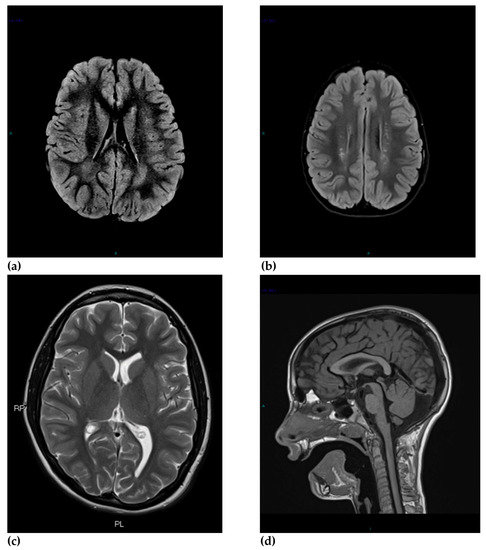

| MRI Findings | ASD Children (n = 117) | HF-ASD (n = 41) | DD-ASD (n = 76) | Typically Developing Children (n = 39) | p |

|---|---|---|---|---|---|

| Abnormal MRI | 64 * | 27 * | 37 | 14 * | <0.05 *,1 |

| Isolated IF | 37 * | 15 * | 22 * | 13 * | All Ps < 0.05 * |

| 2 IFs | 22 | 10 | 12 | 1 | NS |

| 3 IFs | 5 | 2 | 3 | 0 | NS |

| Major abnormal findings | |||||

| Abnormal signal intensities | 26 | 10 | 16 | 4 | NS |

| Retrotrigonal WM intensities | 18 | 4 | 14 | 3 | NS |

| Gliosis | 7 | 6 * | 1 * | 2 | 0.007 * |

| Myelination delay | 3 | 2 | 1 | 0 | NS |

| Abnormal cortical development and/or organization | 2 | 1 | 1 | 1 | NS |

| Atrophy | 1 | 1 | 0 | 0 | NS |

| Corpus callosum anomalies | 5 | 1 | 4 | 0 | NS |

| Ventricular anomalies | 11 | 7 * | 4 * | 3 | 0.049 * |

| Ventricular enlargement and asymmetries | 9 | 6 * | 3 | 0 * | 0.026 * |

| Other ventricular anomalies | 2 | 1 | 1 | 3 | NS |

| Chiari I malformation | 3 | 2 | 1 | 1 | NS |

| Cerebellar anomalies | 4 | 2 | 2 | 0 | NS |

| Minor abnormal findings | |||||

| Dilated Virchow-Robin spaces | 15 | 5 | 10 | 1 | NS |

| Mega cisterna magna | 12 * | 5 | 7 | 0 * | 0.038 * |

| Pineal cyst | 13 | 4 | 9 | 2 | NS |

| Choroid plexus cyst | 2 | 2 | 0 | 1 | NS |

| Arachnoid cyst | 2 | 1 | 1 | 2 | NS |